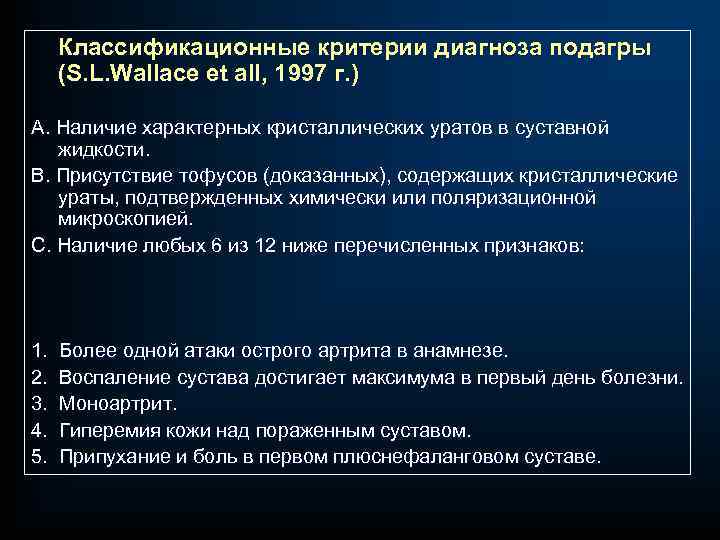

Классификационные критерии диагноза подагры (S. L. Wallace et all, 1997 г. ) А. Наличие характерных кристаллических уратов в суставной жидкости. В. Присутствие тофусов (доказанных), содержащих кристаллические ураты, подтвержденных химически или поляризационной микроскопией. С. Наличие любых 6 из 12 ниже перечисленных признаков: 1. Более одной атаки острого артрита в анамнезе. 2. Воспаление сустава достигает максимума в первый день болезни. 3. Моноартрит. 4. Гиперемия кожи над пораженным суставом. 5. Припухание и боль в первом плюснефаланговом суставе.

Классификационные критерии диагноза подагры (S. L. Wallace et all, 1997 г. ) А. Наличие характерных кристаллических уратов в суставной жидкости. В. Присутствие тофусов (доказанных), содержащих кристаллические ураты, подтвержденных химически или поляризационной микроскопией. С. Наличие любых 6 из 12 ниже перечисленных признаков: 1. Более одной атаки острого артрита в анамнезе. 2. Воспаление сустава достигает максимума в первый день болезни. 3. Моноартрит. 4. Гиперемия кожи над пораженным суставом. 5. Припухание и боль в первом плюснефаланговом суставе.

6. Одностороннее поражение первого плюснефалангового сустава. 7. Одностороннее поражение суставов стопы. 8. Подозрение на тофусы. 9. Гиперурикемия. 10. Ассиметричный отек суставов (рентгенография). 11. Субкортикальные кисты без эрозий (рентгенография). 12. Отрицательные результаты при посеве синовиальной жидкости. Наличие 6 и более признаков подтверждает диагноз подагры. Наиболее достоверны такие признаки, как острый или, реже, подострый артрит, обнаружение уратов в синовиальной жидкости и наличие доказанных тофусов. Дифференциальный диагноз: псевдоподагра; септический артрит; реактивный артрит; ревматоидный артрит

6. Одностороннее поражение первого плюснефалангового сустава. 7. Одностороннее поражение суставов стопы. 8. Подозрение на тофусы. 9. Гиперурикемия. 10. Ассиметричный отек суставов (рентгенография). 11. Субкортикальные кисты без эрозий (рентгенография). 12. Отрицательные результаты при посеве синовиальной жидкости. Наличие 6 и более признаков подтверждает диагноз подагры. Наиболее достоверны такие признаки, как острый или, реже, подострый артрит, обнаружение уратов в синовиальной жидкости и наличие доказанных тофусов. Дифференциальный диагноз: псевдоподагра; септический артрит; реактивный артрит; ревматоидный артрит